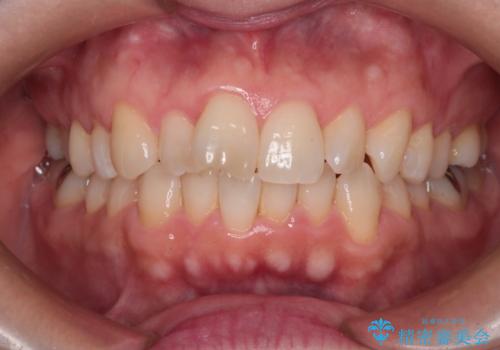

【インビザライン 】前歯のガタガタを治したい

- 前歯のガタガタを主訴に来院されました。

インビザライン で治療しました。途中は使用時間が20時間を切ることもありましたが、それでも頑張って使っていただき1年半で矯正終了することができました。